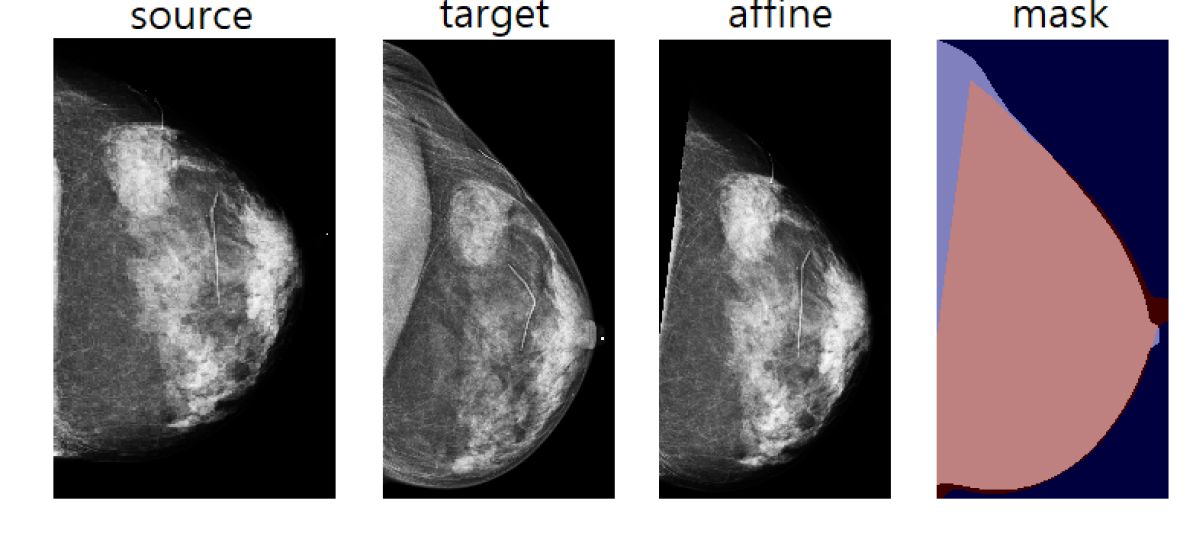

When a patient has multiple exams, the images for each view taken at different times can appear at different angles, sizes, or even different resolutions. We align the images within each pair before feeding them to our model in order to detect local changes without requiring the model to learn alignment. Concretely, we use two CNN models for geometric matching Rocco et al. (2017), one trained using VGG Simonyan and Zisserman (2014) and one using ResNet-101 He et al. (2016), for feature extraction. These models take a pair of images as input and output the parameters of an affine transformation to align the images from the prior exams to images from the recent exams. Using two transformation parameters from both models, we choose the one with better IoU of the nonzero masks of the registered source and target images (cf. \figurereffig:alignment).

Refer to caption

Figure 1: Alignment of image pairs. Source is the prior image, target is the current image, affine is registered source and mask represents the overlay of target and affine.